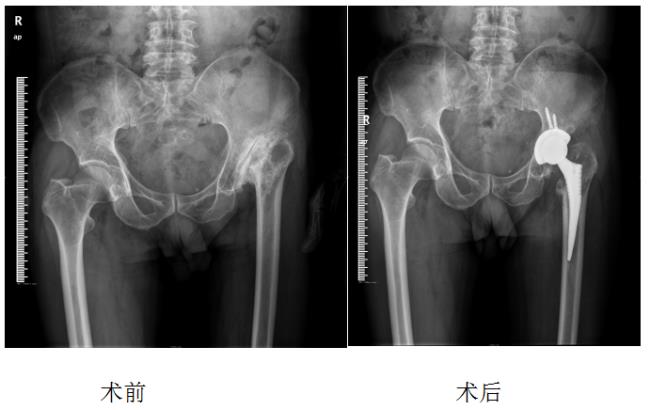

治疗复杂髋部疾病如先天性髋关节发育不良(DDH)、强直髋(强直性脊柱炎)、髋关节置换术后翻修、髋关节置换术后感染等。

1、先天性髋关节发育不良:

术后5天基本恢复正常